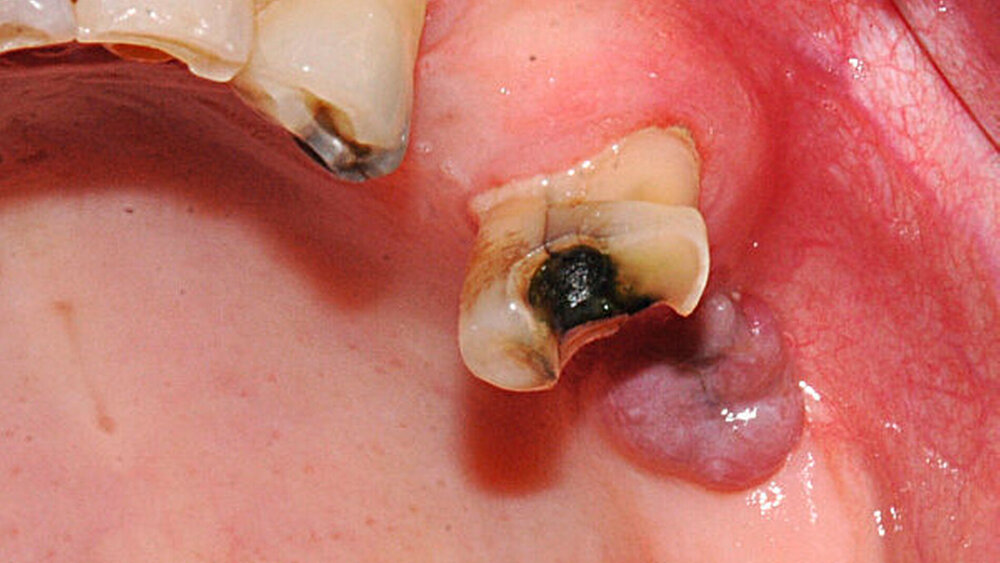

Klinisch wird für enoral gelegene braune Tumore beschrieben, dass sich diese als schmerzhafte, harte und klar palpable Schwellungen darstellen [Triantafillidou, Zouloumis et al., 2006], meist steht jedoch die Symptomatik des Hyperparathyreoidismus im Vordergrund.